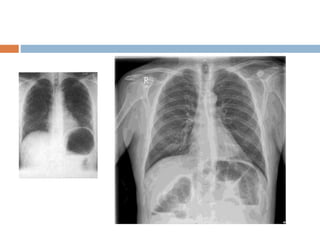

 This is chest radigraph , PA view with normal

exposure , no rotation and without any

apparent bony abnormality . Trachea is placed

centrally and lung fields are clear with normal

broncho- vescicular markings . Cardivascular

silhoutte is within normal limits with normal

cardiothoracic ratio. Mediastinum, costo

phrenic , cardio phrenic angles , dome of

diaphragm and soft tissue shadow within

normal limits .